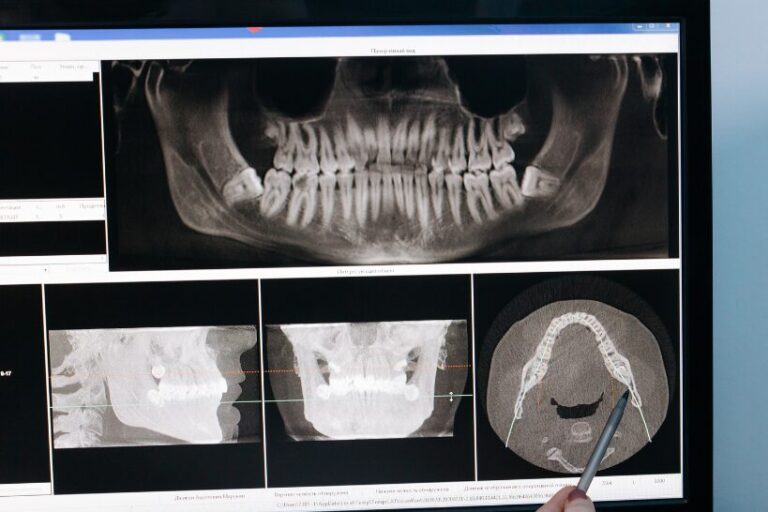

How Dr. Lordo Approaches Treatment

Dr. Lordo utilizes advanced diagnostic techniques to pinpoint the exact source of the dysfunction. No two cases of TMD are identical; therefore, no two treatment plans are the same.